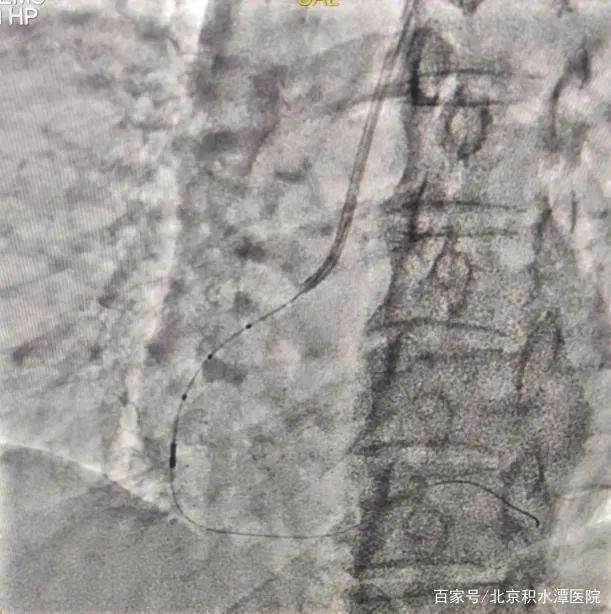

但在上台后,发现3个月过后,左前降支血管已经完全闭塞,手术难度远远超出预期,无法判断血管走行和方向。所以决定采用微量造影剂的办法进行介入治疗。刘教授凭借经验,在只应用少许造影剂的情况下,不断更换导丝进行尝试后,终于通过闭塞病变到达血管远端。导丝通过闭塞病变后,不再使用造影剂,使用IVUS检查发现,闭塞处有严重钙化斑块。通过IVUS明确支架植入位置和大小,最终成功植入支架。手术过程共使用造影剂约20ml。术后监测患者血肌酐,无明显改变并且处于稳定状态。患者也高高兴兴地出院了。

在对李女士的治疗过程中,刘巍教授在患者的第一次冠状动脉造影的影像指导下,经过远端桡动脉入路,将指引导管放置在右侧冠状动脉开口,导丝送至血管远端,但是由于患者病变弥漫,狭窄严重,并且开口就有病变,指引导管稍微深插就会出现压力下降和心电图ST段抬高,手术的难度超出预期。这时使用IVUS进行血管内超声检查,结果显示,右冠状动脉中段最小管腔面积仅2.0mm2,并且可见超声衰减斑块和高负荷脂质斑块,并且病变比预想的还要弥漫和严重。刘教授团队根据边支定位以及IVUS导管标记点定位,对狭窄病变进行充分预扩张,复查IVUS提示扩张效果满意后,根据IVUS定位精准地植入了两枚支架,再次复查IVUS提示支架膨胀及贴壁良好,无边缘夹层等情况。手术过程顺利,全程未使用一滴造影剂就成功完成了支架的植入。术后患者没有出现任何不适。手术过程不到30分钟,患者术后症状立刻缓解。第3天就出院了。

但在上台后,发现3个月过后,左前降支血管已经完全闭塞,手术难度远远超出预期,无法判断血管走行和方向。所以决定采用微量造影剂的办法进行介入治疗。刘教授凭借经验,在只应用少许造影剂的情况下,不断更换导丝进行尝试后,终于通过闭塞病变到达血管远端。导丝通过闭塞病变后,不再使用造影剂,使用IVUS检查发现,闭塞处有严重钙化斑块。通过IVUS明确支架植入位置和大小,最终成功植入支架。手术过程共使用造影剂约20ml。术后监测患者血肌酐,无明显改变并且处于稳定状态。患者也高高兴兴地出院了。